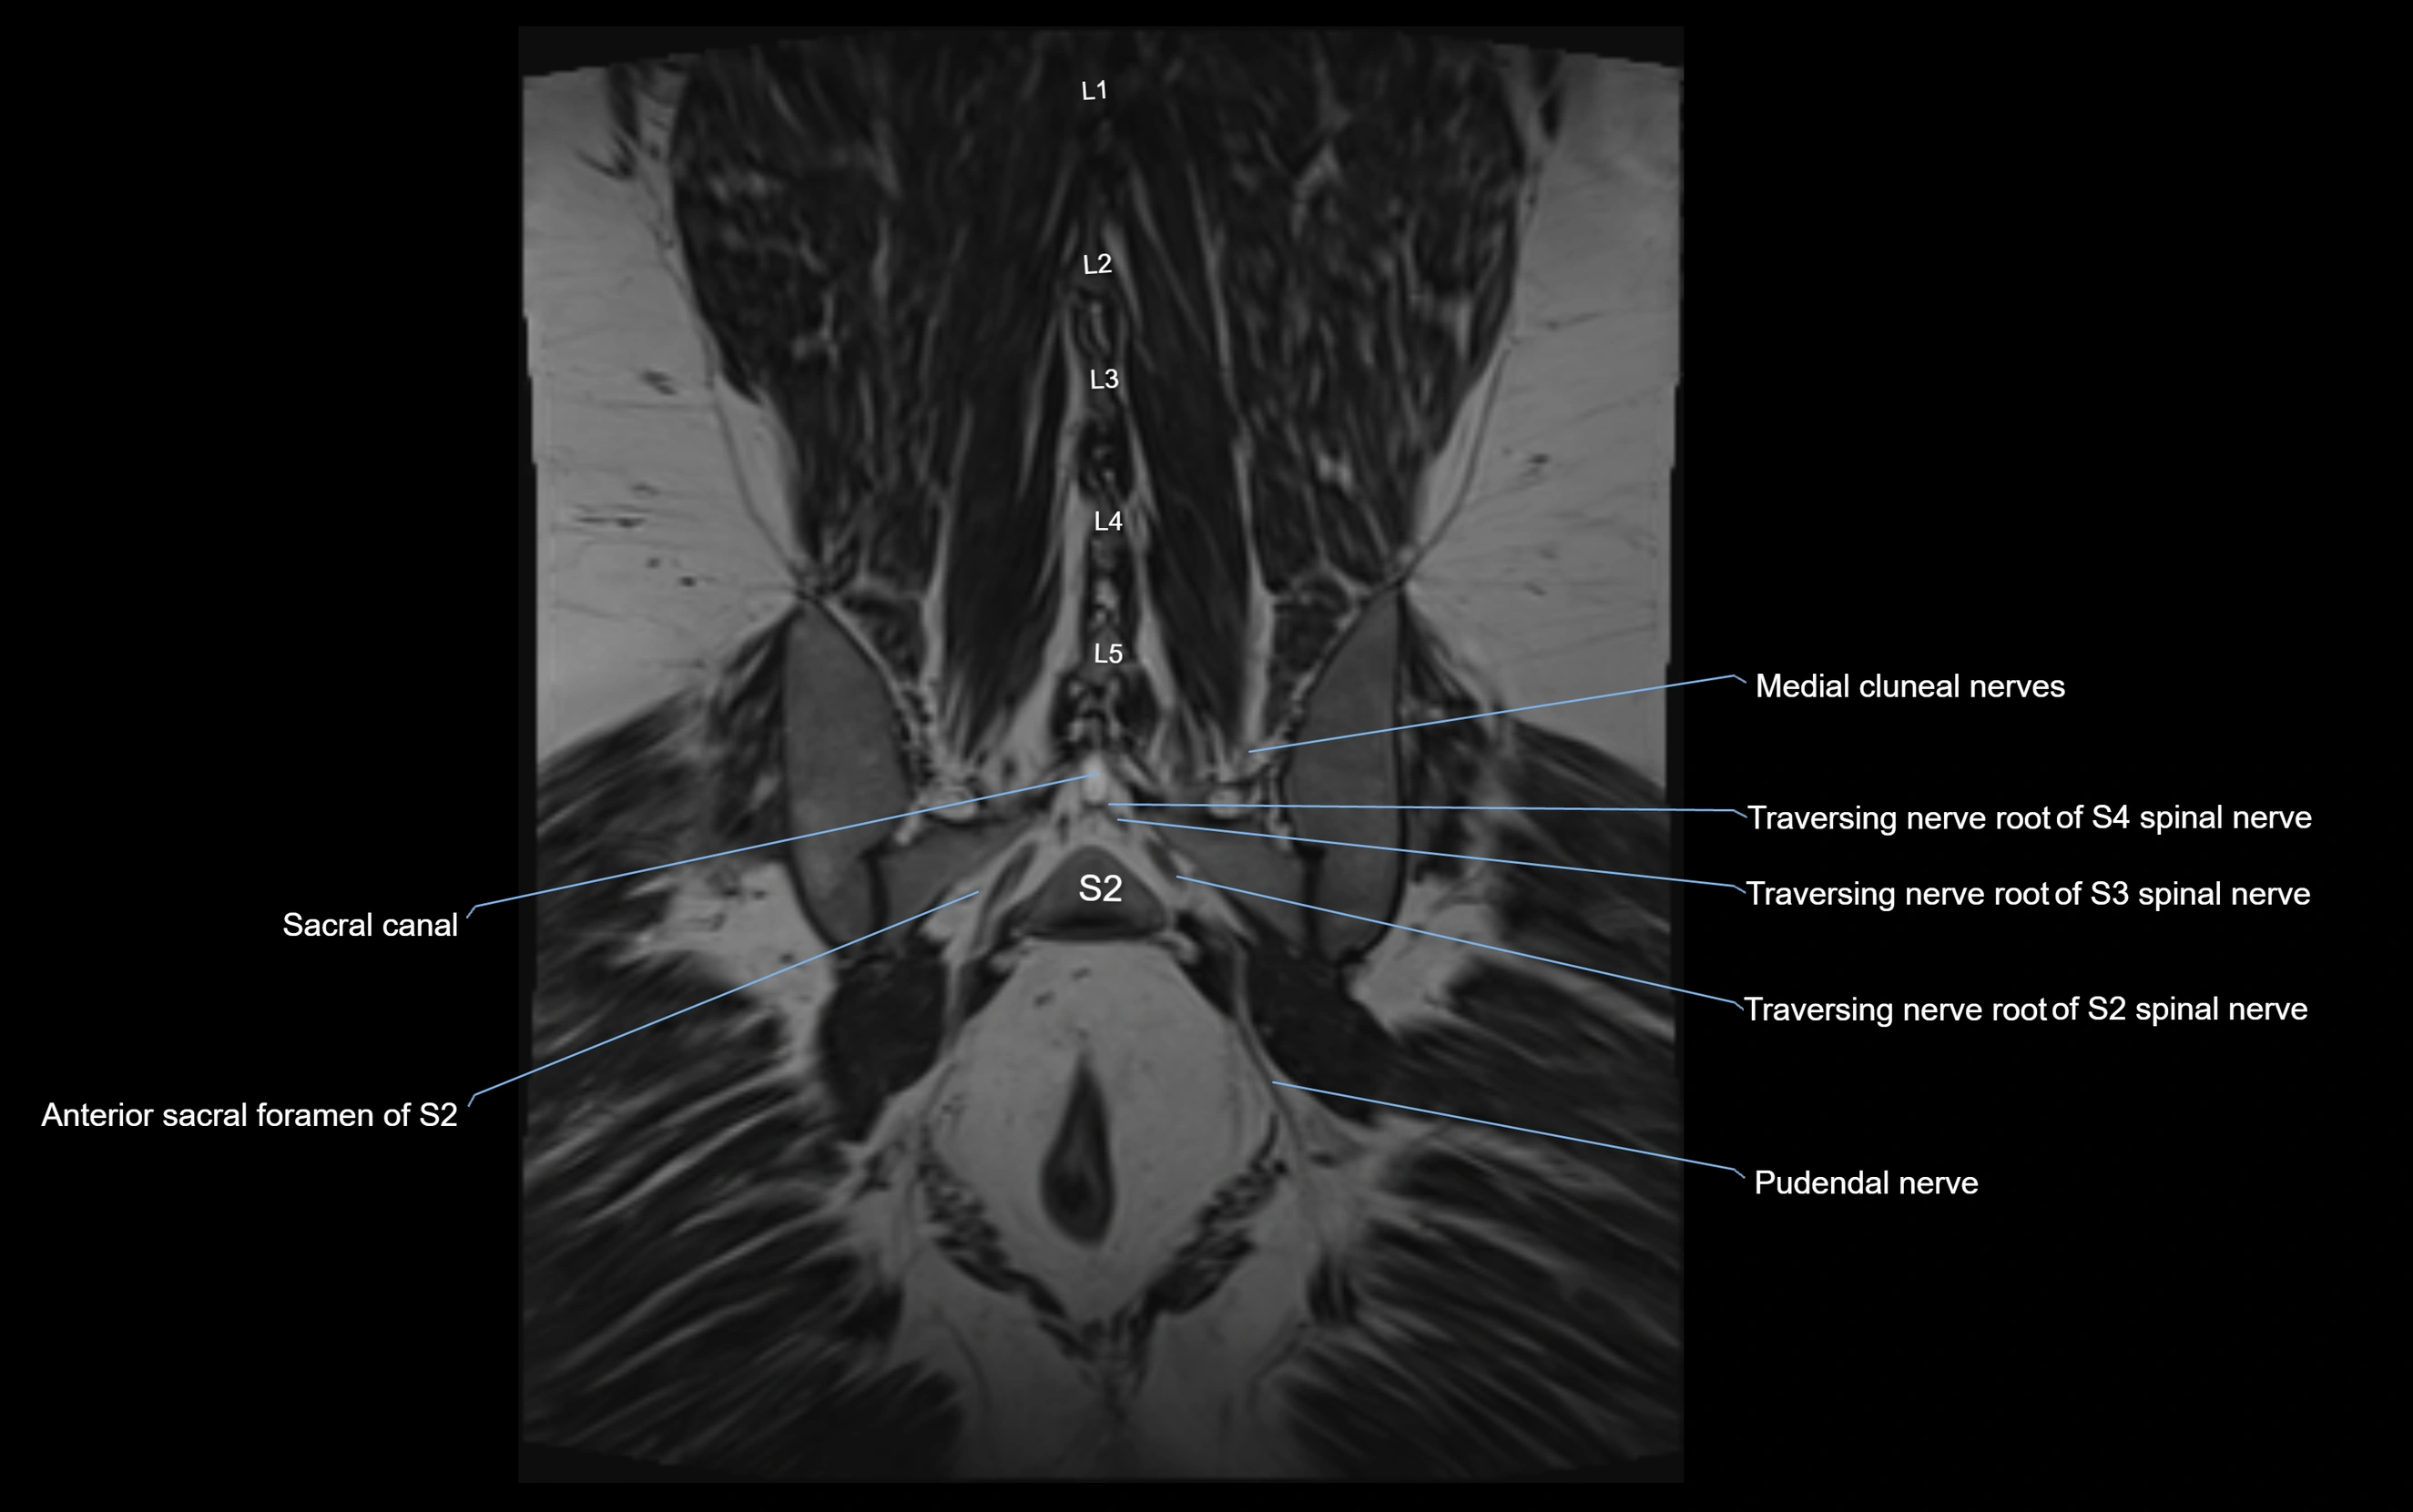

MRI Appearance

T1-weighted images:

• Nerve appears as a very thin low-to-intermediate signal intensity structure

• Surrounded by bright fat, aiding visualization

T2-weighted images:

• Nerve shows intermediate to mildly hyperintense signal compared to muscle

• Pathological involvement appears brighter

STIR (Short Tau Inversion Recovery):

• Normal nerve appears dark

• Inflamed or entrapped nerve appears bright hyperintense

T1 Fat-Sat Post-Contrast:

• Normal nerve enhances minimally

• Pathologic nerve (neuritis, entrapment, tumor infiltration) shows focal or diffuse enhancement

3D T2 SPACE / CISS:

• Nerve appears intermediate to mildly hyperintense compared to muscle

• Surrounded by bright fat or CSF, improving visualization

• Best sequence for mapping small pelvic nerves such as the anococcygeal